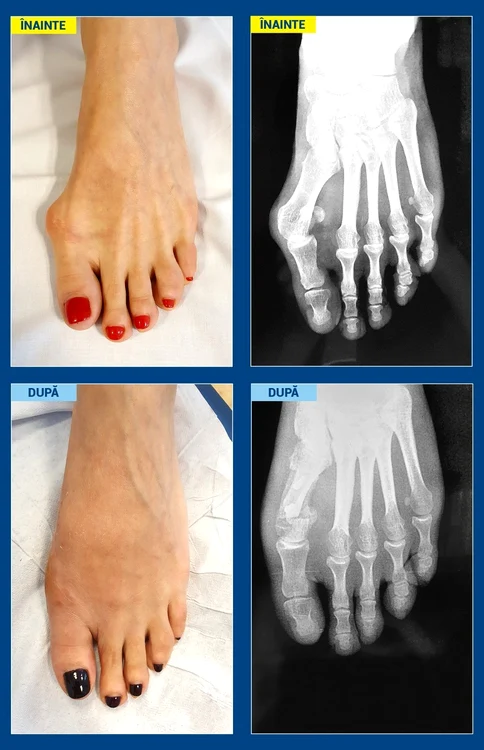

Legendă foto: Pacientă, 43 de ani, profesoară de balet/balerină Înainte: Aspect clinic şi radiologic preoperator După: Aspect clinic şi radiologic la o lună de la operaţie.